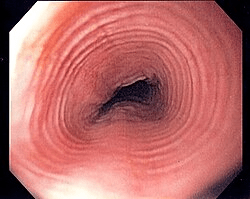

A 29-year-old man presents with intermittent solid-food dysphagia and several episodes of food impaction requiring emergency evaluation. He has a history of asthma and seasonal allergies.

Upper endoscopy shown below.

What is the most likely diagnosis?

Eosinophilic esophagitis